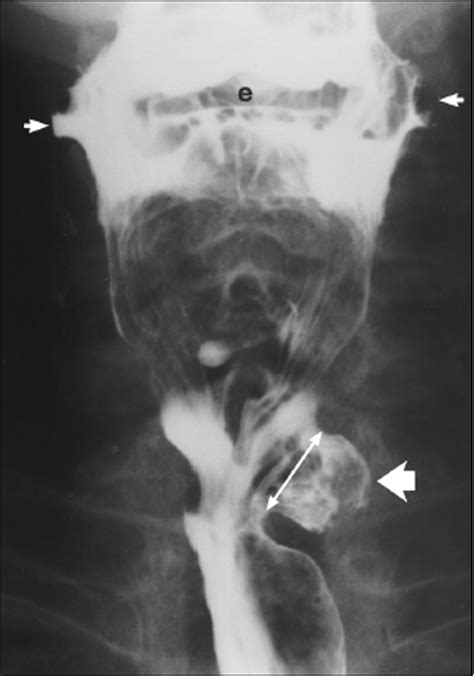

Voiding Cystourethrogram (VCUG) An X-ray procedure that shows the bladder filling and emptying; excellent for identifying diverticula.